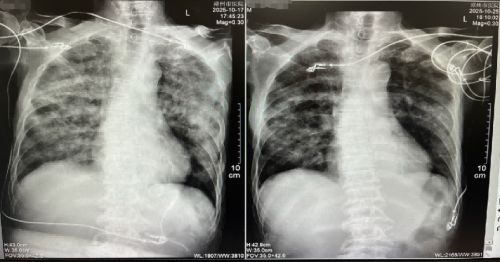

抗结核后复查胸部CT较前好转。